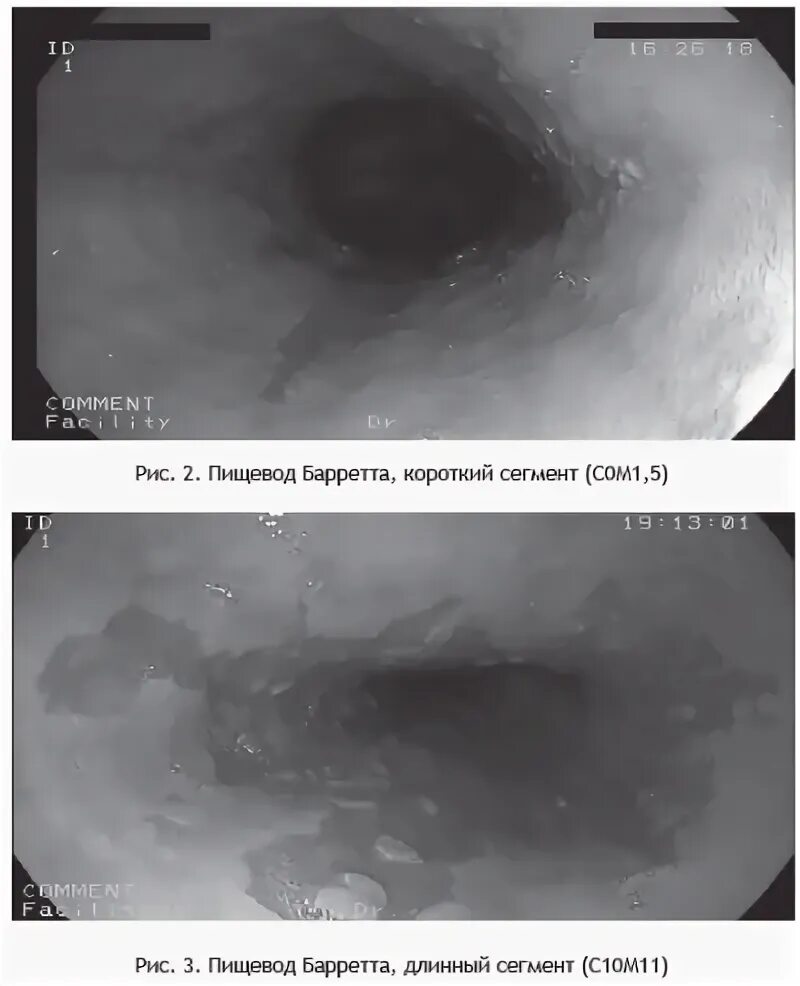

Барретта симптомы и лечение